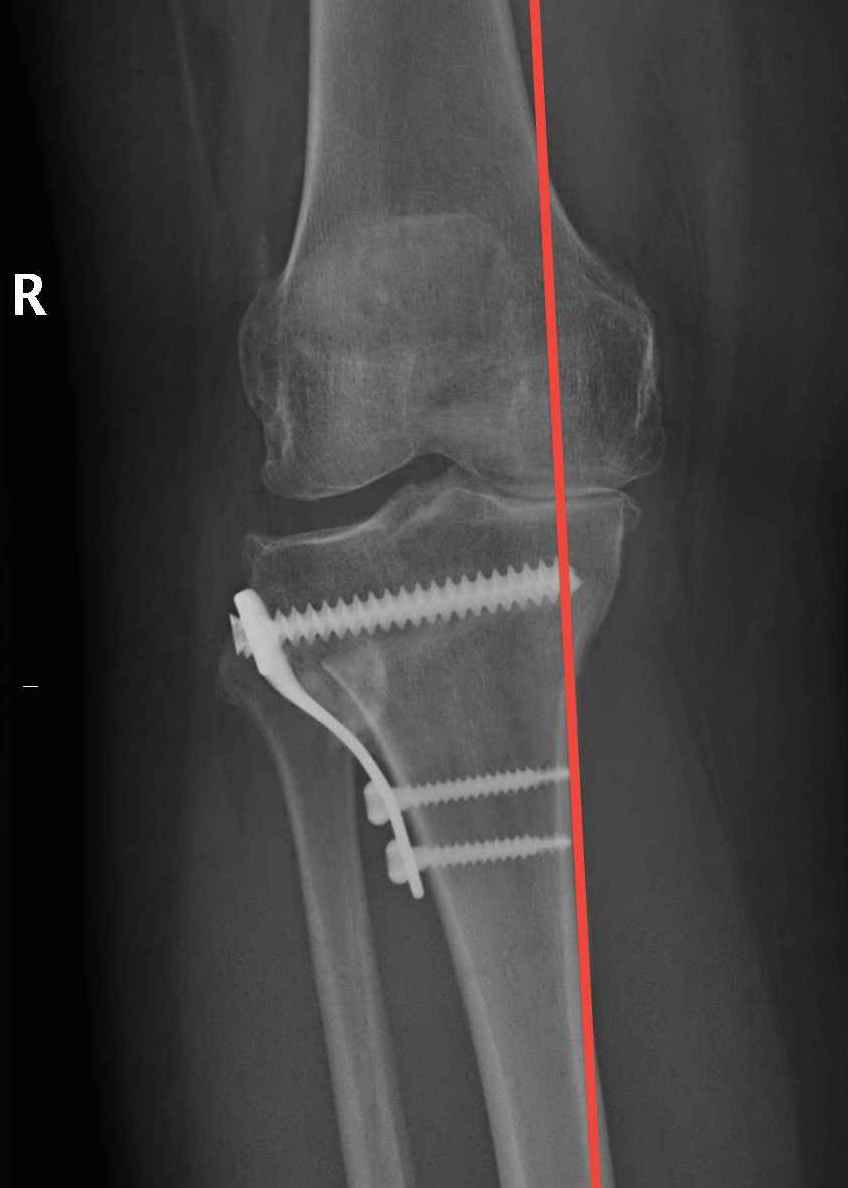

Check correction

- drop rod

- Fujisawa point

Stabilise osteotomy with plate